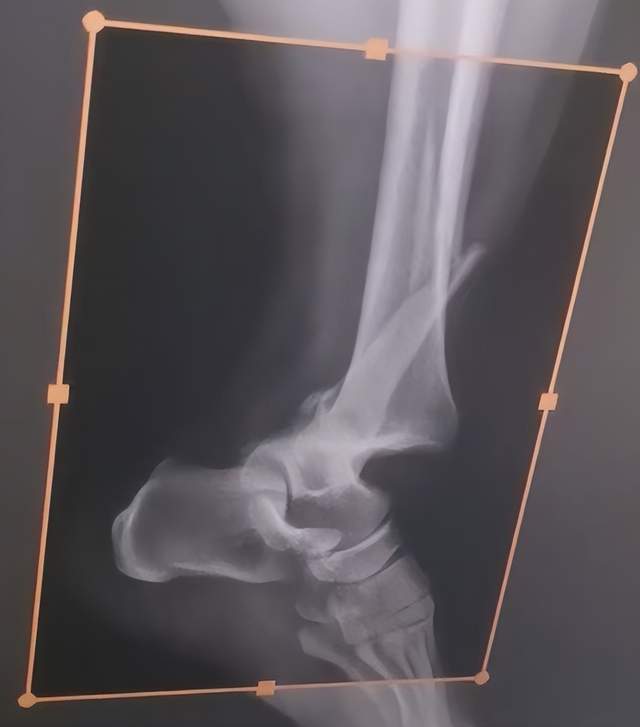

术前术后影像对比

入院检查显示:

右踝关节脱位:关节结构完全错位,稳定性丧失;

右侧腓骨远端骨折:骨折线清晰,断端移位明显;

下胫腓联合分离:韧带损伤导致关节连接异常。